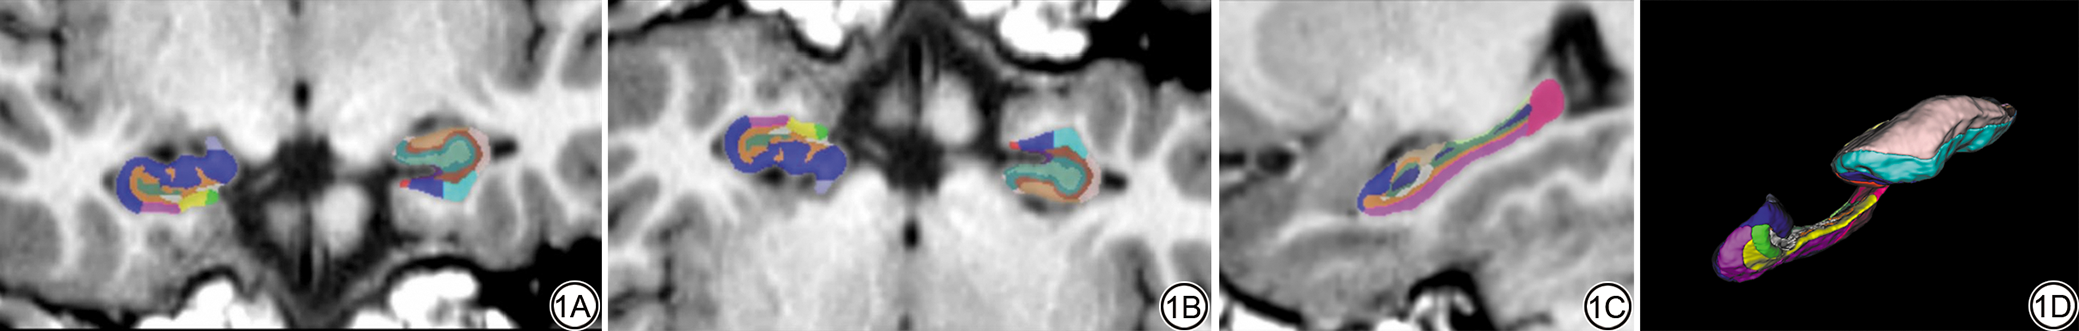

所有3D-T1WI图像数据传输至联影智能脑分割软件进行处理。使用联影智能科研平台(uAI research portal, uRP;联影智能医疗科技有限公司,上海)[12]自动识别3D-T1WI序列,并基于VB-Net深度学习模型进行全脑结构分割,获取脑组织分割图像及双侧海马体积测量结果[10]。计算双侧海马体积占全脑体积的比值(海马体积占比)(图1)。

图1  T1WI-3D智能脑分割海马的冠状位(1A)、轴位(1B)、矢状位(1C)及重建图像(1D)。

Fig. 1  Coronal view (1A), axial view (1B), sagittal view (1C), and reconstructed image (1D) of the hippocampus from T1WI-3D intelligent brain segmentation.